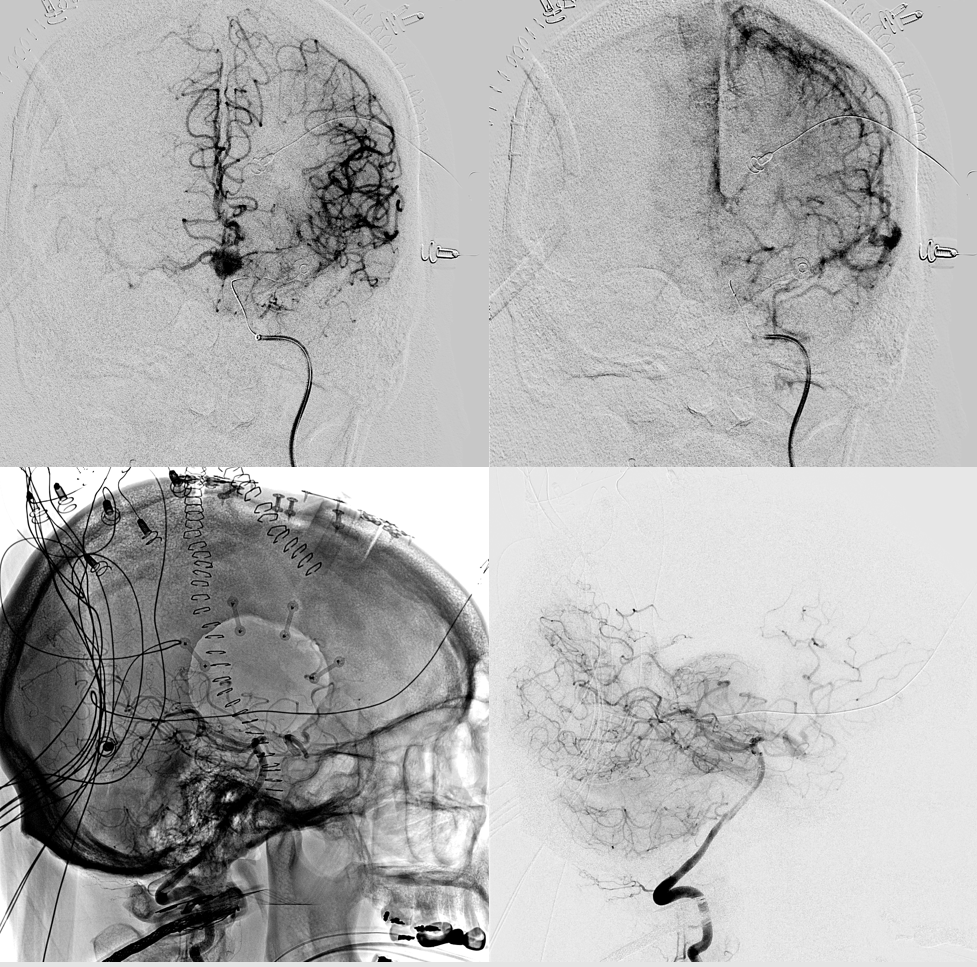

Angio intraop post bypass- STA-MCA working

ACA-ACA did not have flow at this point. Tested by a left A2 BTO. How does that test for bypass patency?

STA-MCA bypass, right ophthalmic, and right PCOM not enough to supply right ACA at this stage — tested by left supraclinoid bypass — what is the rationale there?

Bilateral CBCT Injections. A big bonus — the ACA-ACA bypass now seems to be patent! Cant see that from 2D images really at this stage. We did not realise this at first but became clear later

A3-A3 bypass more images

Stereo views of the two craniotomies, with translucent and sonolucent closure